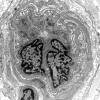

PERIPHERAL NEUROPATHY

11 VASCULITIS - VASCULOPATHY

2 Vasculopathy (7)